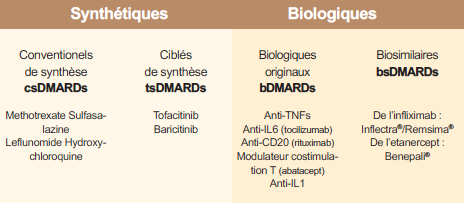

Tableau 2 : La prise en charge de la polyarthrite rhumatoïde (PR) repose essentiellement sur l'utilisation des traitements de fond appelés "disease-modifying antirheumatic drugs" (DMARDs)

Depuis 2014, le tocilizumab (inhibiteur de l’IL-6) et l’abatacept (inhibiteur de la costimulation CPA-lymphocytes) sont devenues disponibles par voie sous-cutanée en injection hebdomadaire. Depuis cette date, les biosimilaires sont apparus et sont utilisables en France : le CP-T13 (INFLECTRA® et REMSIMA®) qui est un infliximab IV biosimilaire du REMICADE® ; le SB4 (BENEPALI®) qui est un étanercept biosimilaire de l’ENBREL®. Les biosimilaires ont un coût inférieur à la biothérapie princeps, par exemple de 15% à ce jour pour le BENEPALI® (Tableau 2).

La principale nouveauté thérapeutique réside dans le développement des traitements de fond conventionnels ciblés qui sont des petites molécules ayant des cibles thérapeutiques spécifiques. Ce sont les inhibiteurs des kinases et en l’occurrence des JAK-kinases (4 isotypes JAK1, JAK2, JAK3 et TYK2). Les inhibiteurs des JAK inhibent directement la production des cytokines JAK dépendantes (IFN-γ, IL-6, IL-12, IL-23) et indirectement celle d’autres cytokines pro-inflammatoires (TNF). Le tofacitinib (XELJANZ®) est un inhibiteur de JAK1 et JAK3 qui est démontré efficace dans la PR sur le plan clinique et structural. Après un refus initial en 2013, ce médicament (en association avec le méthotrexate) vient de recevoir un avis favorable de l’EMA le 26 janvier 2017, alors qu’il était déjà commercialisé aux Etats-Unis, au Canada et en Suisse. Le baricitinib est un inhibiteur de JAK1 et JAK2, et son développement est avancé. L’étude RA-BEAM a démontré l’efficacité clinique et structurale du baricitinib dans la PR en échec au méthotrexate et le baricitinib dans cette étude apparait au moins équivalent sinon supérieur cliniquement à l’adalimumab.